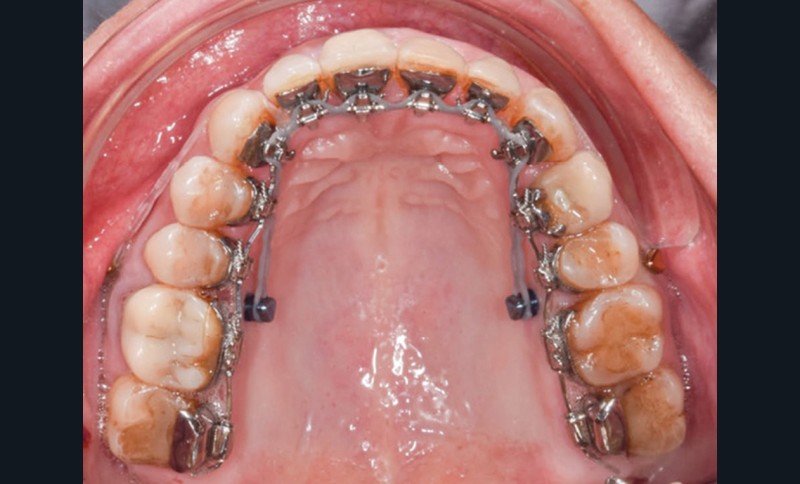

Séquences thérapeutiques (fig. 4)

La préparation de la denture consiste en un alignement et un nivellement. En orthodontie linguale totalement individualisée, le nivellement de la courbe de Spee est facilité par la présence des bases des attaches sur les incisives maxillaires qui provoquent une égression des secteurs postérieurs et une ingression et vestibulo-version des incisives mandibulaires. L’utilisation d’arcs acier ribbonwise .016 x .024 est également efficace pour ce nivellement [3].

La correction de la denture passe par la correction des torques incisifs grâce à des arcs acier maxillaires .016 x .024 extra torque 13° puis extra torque 21° qui permet le rétablissement d’un surplomb et par ce fait le déverrouillage mandibulaire.

La distalisation maxillaire par ancrages squelettiques temporaires peut alors commencer, 4 minivis sont mises en place pour une correction bilatérale : deux minivis sont placées en vestibulaire (8 mm) et deux minivis en palatin (10 mm) entre la seconde prémolaire et la première molaire maxillaire [4]. La distalisation peut ainsi avoir lieu progressivement, grâce à des chaînettes en double câble, vestibulaire et palatine.

Cette technique est associée à une mécanique de traction interarcade de classe II, l’action est surtout maxillaire puisqu’il y a présence d’un implant en 36. La traction élastomérique sera de 6 oz à droite et de 3,5 oz à gauche.

Les finitions et l’intercuspidation sont réalisées avec des arcs TMA .018 x .018 et avec des tractions interarcades verticales.